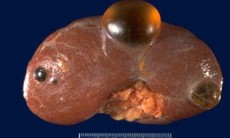

Tại Bệnh viện An Bình, số trường hợp bệnh nhân được chuyển đến vì "nang thận" nhưng thực chất là khối u thận dạng nang đang có xu hướng gia tăng. Những tổn thương này có hình ảnh ban đầu khá giống nang đơn thuần nhưng lại sở hữu đặc điểm nguy hiểm hơn như vách dày, vôi hóa, tăng sinh mạch máu hoặc chứa mô đặc bên trong – những dấu hiệu gợi ý ung thư tế bào thận dạng nang, một thể ác tính khó phát hiện bằng siêu âm thông thường.

Bác sĩ Phong cho biết, từng tiếp nhận những bệnh nhân mang theo kết quả siêu âm của năm trước chỉ ghi nhận "nang thận". Tuy nhiên, khi tái khám tại Bệnh viện An Bình, tổn thương đó lại xuất hiện vách ngăn, dày bất thường và tăng sinh mạch máu - yếu tố nguy cơ cao của ung thư thận. Một số trường hợp, khối u đã phát triển đủ lớn khiến ê-kíp buộc phải thực hiện phẫu thuật cắt một phần thận để lấy trọn tổn thương nhưng vẫn bảo tồn tối đa chức năng nhu mô thận còn lại.

Đối với những tổn thương phức tạp hoặc nghi ngờ ung thư, phẫu thuật bảo tồn thận luôn được ưu tiên, đặc biệt khi khối u còn nhỏ. Kỹ thuật này đòi hỏi kinh nghiệm cao, bởi bác sĩ vừa phải loại bỏ hoàn toàn tổn thương ác tính, vừa phải giữ lại phần thận lành. Nếu phát hiện muộn, khi khối u đã lớn hoặc xâm lấn, bệnh nhân buộc phải cắt toàn bộ thận – điều đáng tiếc có thể tránh được nếu được chẩn đoán sớm.